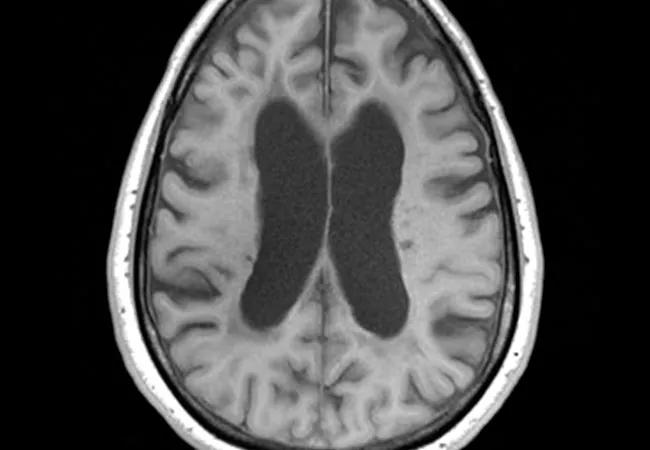

Patient disability levels were assessed every three months, and brain MRIs were taken at baseline and at 12, 24 and 36 months.

On other secondary outcome measures, although siponimod had no significant effect on maintenance of walking speed (as assessed by timed 25-foot walk test), it significantly reduced the increase in T2 lesion volume on MRI from baseline to 24 months compared with placebo. “Loss of brain volume is an important marker for tissue damage in MS,” Dr. Fox explains.